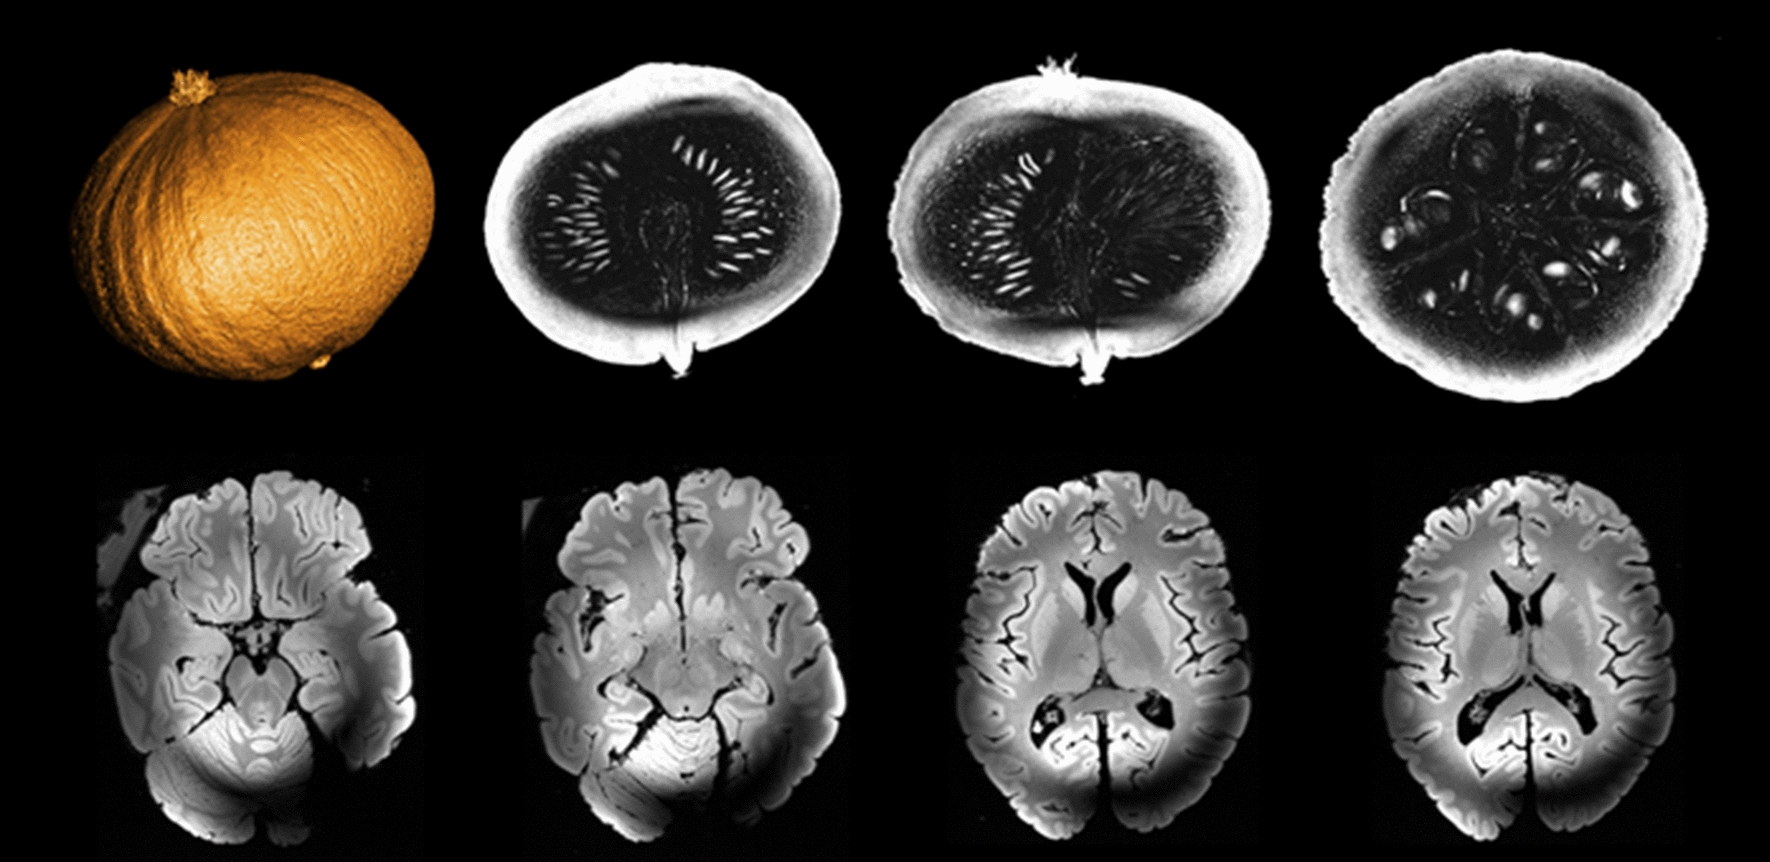

After ensuring that gradient activity would not pose a serious risk to the magnet, first images were acquired on a pumpkin and on an ex-vivo brain at 11.7 T in 2021 [17]. Figure 10 shows different slices (axial, coronal and sagittal on the pumpkin, only axial for the ex-vivo brain) acquired with a 3D GRE sequence at 0.4 mm isotropic resolution with the service volume coil. The RF field inhomogeneity artefact is clearly visible on the ex vivo acquisition and is inherent to the use of high fields and volume coils. Those acquisitions were a milestone in the history of the project confirming that Iseult was no longer just a magnet but had become an MRI machine. More quantitative measurements followed. The same (traveling) spherical phantom was scanned at 3 T, 7 T and 11.7 T at NeuroSpin CEA, at 7 T and 9.4 T at the University of Maastricht, and finally at 7 T and 10.5 T at the Center for Magnetic Resonance Research of the University of Minnesota [9]. SNR measurements at the center of the phantom were performed in quasi-identical conditions (phantom, positioning, MR protocol, temperature and volume coil). Results revealed an SNR trend proportional to \({B}_{0}^{1.94}\), in good agreement with theory, confirming this time quantitatively that Iseult delivers its MR potential.

Fig. 10

First images acquired on a pumpkin (top row) and ex-vivo brain (bottom row) at 11.7 T with the service volume coil (October 2021). 3D-GRE sequence parameters were: TR = 20 ms, TE = 1.8/2.5 ms (pumpkin/brain), 4 averages, 512 × 512 × 512 matrix